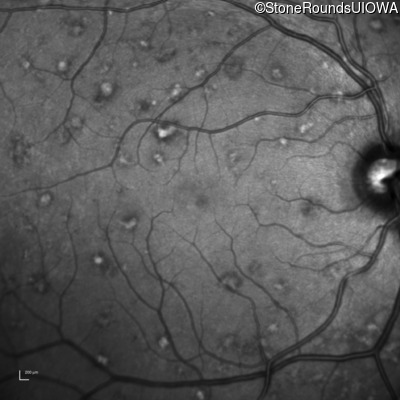

Infrared Fundus Photograph - Left - 20/15 -2 sc

Exemplar